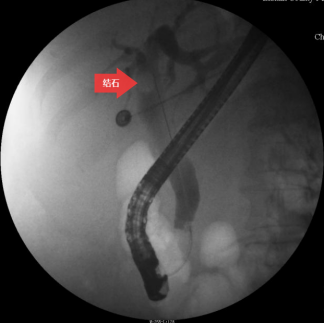

圖三:膽道造影

第三步:插管成功后,注入造影劑,造影顯示膽總管結(jié)石。(箭頭所指為膽總管結(jié)石)